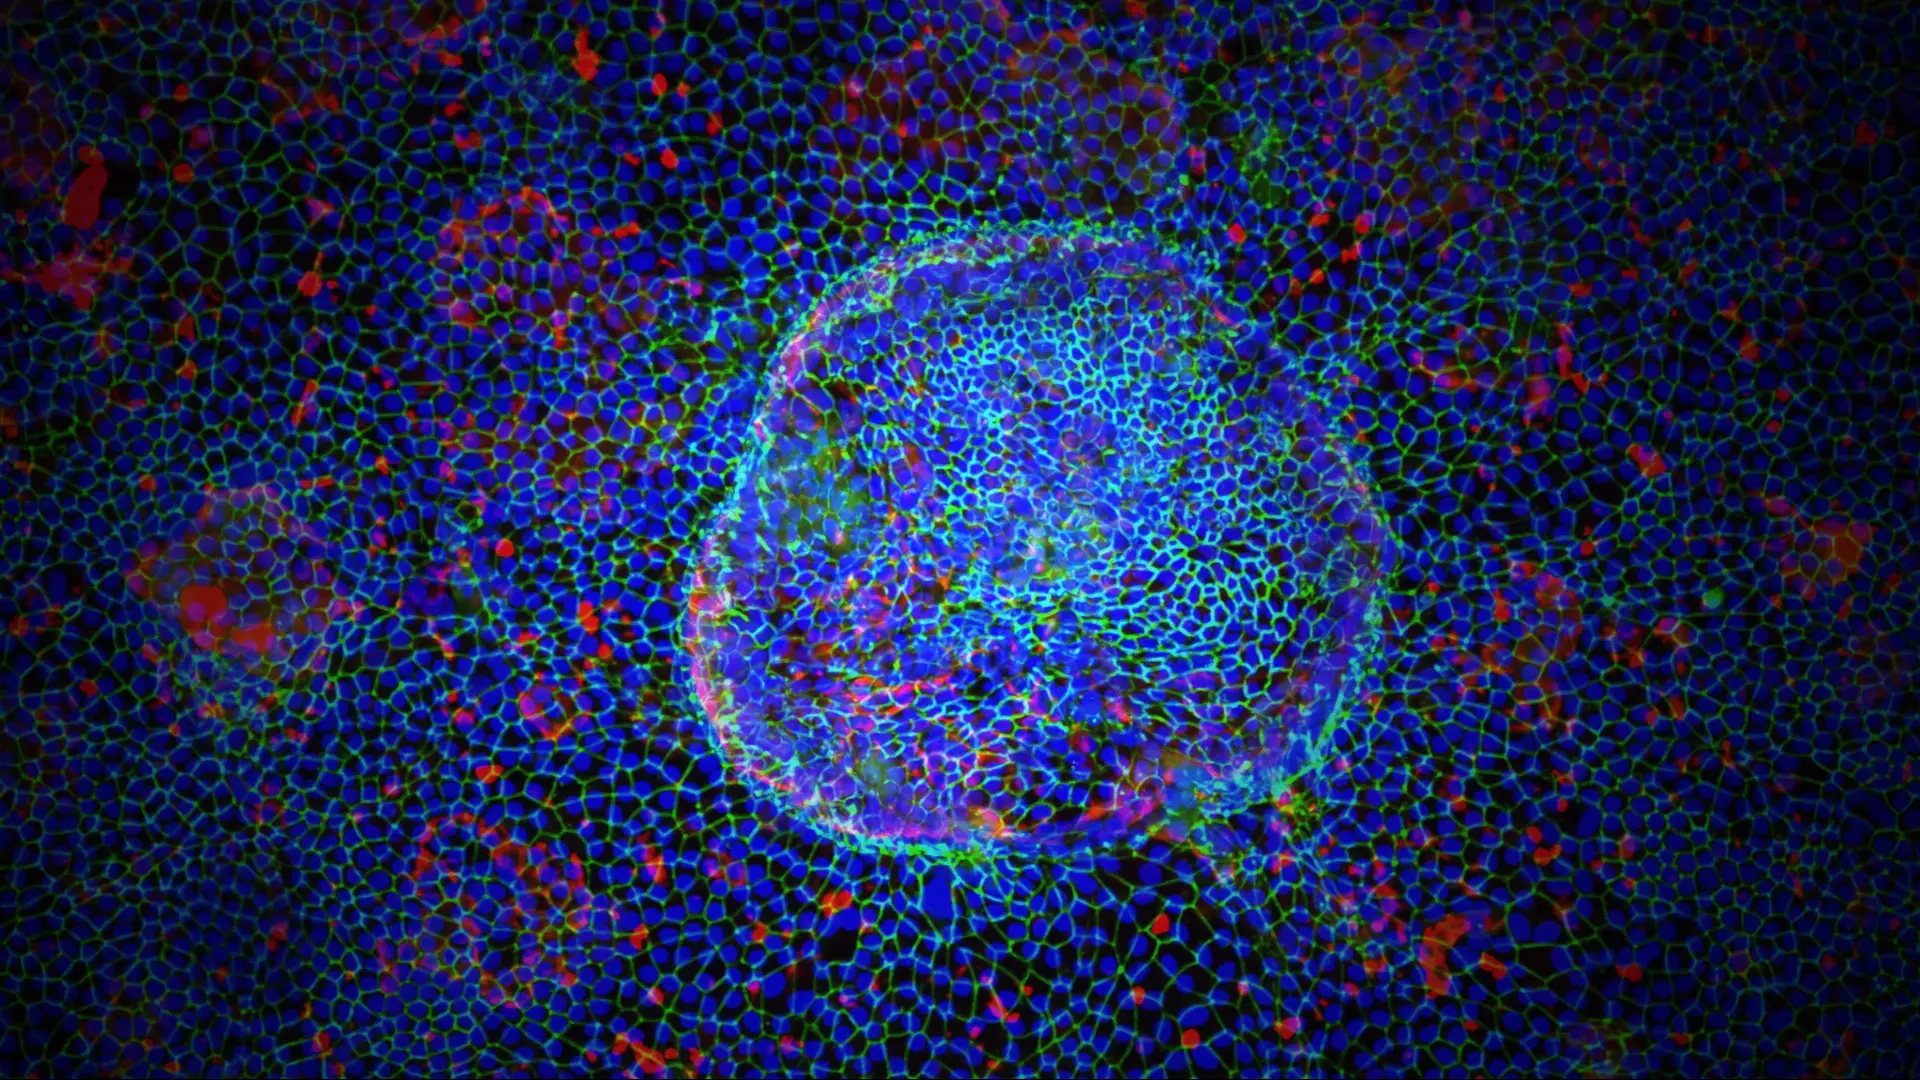

Specifically, the Loeb Center has been at the forefront of exploring the role of microglia—the brain’s immune cells—in the development of AD, and by integrating large-scale molecular data from patients using artificial intelligence (AI), they have been able to identify new drug targets. In the next decade, Dr. Goate believes their work holds great potential for uncovering possible new treatments for patients.